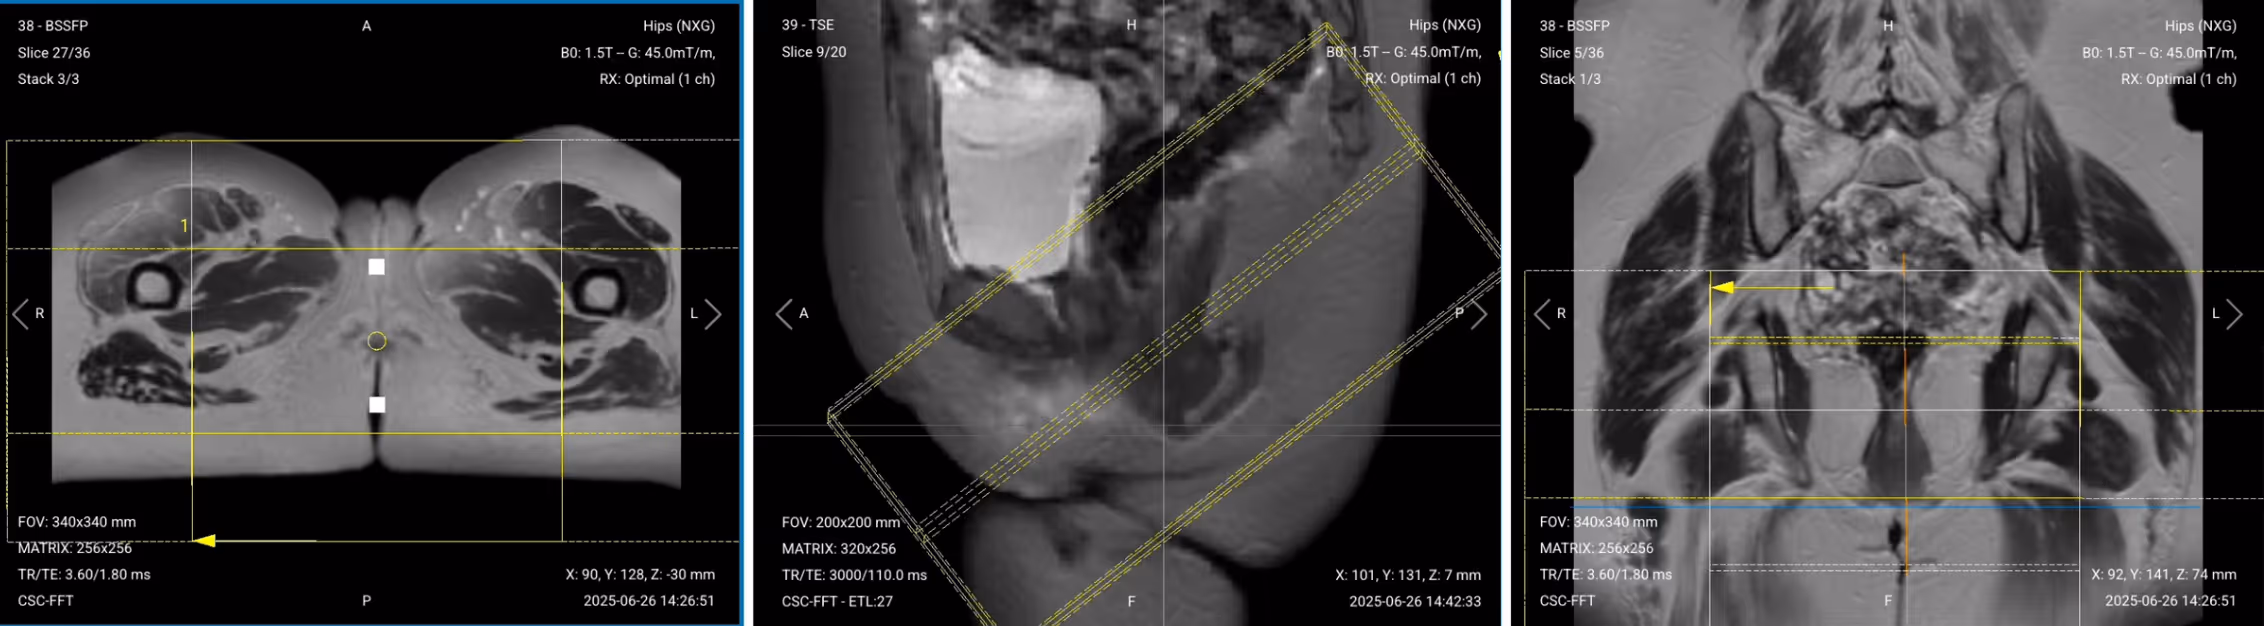

Once acquired, upload the initial localizer images into the three viewports.

Then, scroll through each of the image stacks to locate a central slice that clearly shows the anatomy of the anal canal.

✅ Correct Setup of Localizer Images for Anal Fistula MRI: